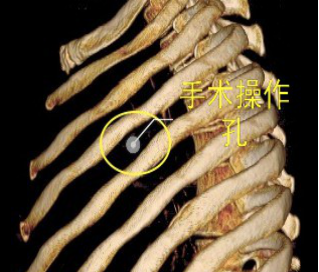

當(dāng)前,絕大多數(shù)的肺大泡手術(shù)均可在電視胸腔鏡(VATS)下完成,2/3的患者術(shù)后癥狀明顯改善。與家長溝通后,鄧意平成功為小王開展單孔胸腔鏡下左側(cè)肺大泡切除術(shù)。

較兩孔、多孔胸腔鏡手術(shù)或傳統(tǒng)手術(shù),單孔手術(shù)具有創(chuàng)傷更小、出血更少、術(shù)后疼痛更輕、瘢痕小、切口更加美觀、術(shù)后恢復(fù)快、住院時間短等優(yōu)勢。但手術(shù)中所有器械(包括觀察鏡、吸引器、電凝鉤、切割閉合器、雙關(guān)節(jié)等各種操作器械)都要是從一個小“孔”進入,器械之間的互相干擾,同時器械與觀察鏡幾乎平行,視野非常狹窄,手術(shù)難度明顯,增加極其考驗醫(yī)生的技術(shù)。